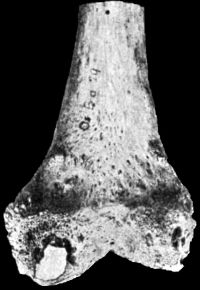

120.Upper End of Femur in advanced Arthritis Deformans of Hip226

121.Femur in advanced Arthritis Deformans of Hip and Knee Joints227